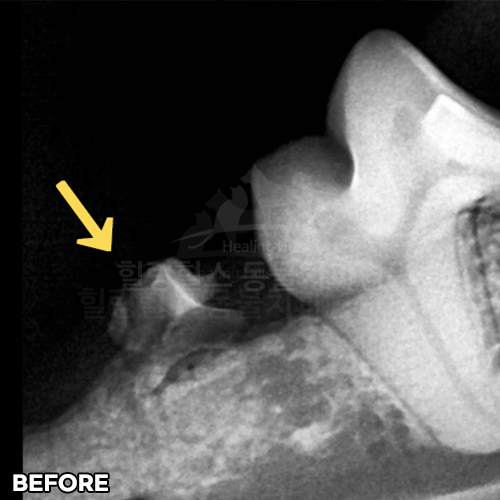

최고 난이도 강아지신경치료 - 꽉막힌 근관&치수괴사! 커다란 반려견치근단농양! 녹아내린 턱뼈! 치통으로 사나워진 모습! 강아지 신경치료 & 치주치료 한달 뒤 좋아졌어요!